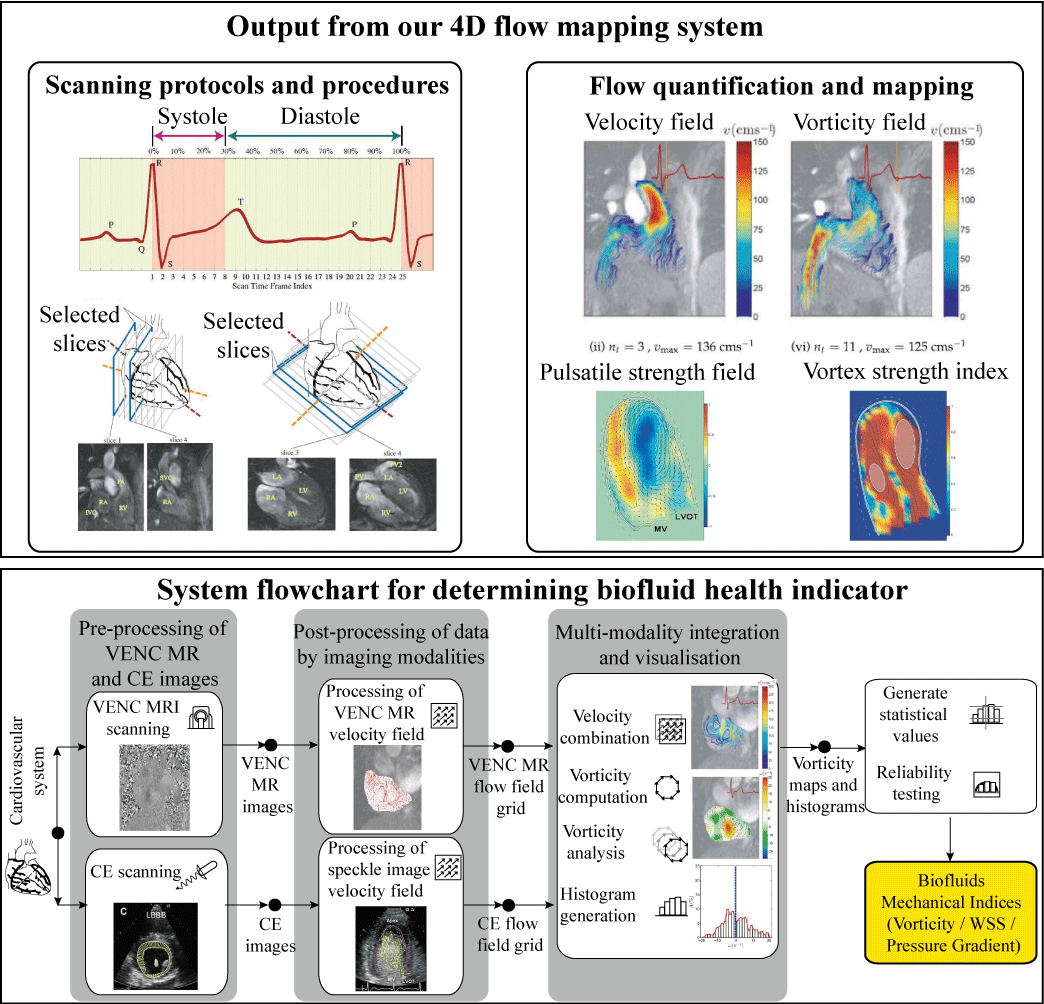

我们得出的心脏的血流特性,基于相位对比度磁共振成像或造影超声心动图。然后,基于生物流体场和派生的流动参数,我们将实现一个心内室可视化系统加上血流动力学指标为流动检查,具体流程如如图5所示。

图5 相位对比MRI或超声造影技术进行流量可视化和涡度的生物流体力学参数的推导,壁面剪切应力和压力梯度,作为生物制剂的健康指标